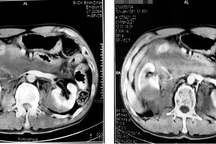

Khi đến Bệnh viện Bình Dân, người bệnh trong tình trạng đau nhức vùng hông lưng hai bên, đau tăng khi ấn vào. Kết quả siêu âm, chụp X-quang và CT ghi nhận thận phải ứ nước độ 1, hai thận có 4-5 viên sỏi phức tạp. Kích thước sỏi lớn nhất khoảng 14x20x20mm.

Sau khi nghiên cứu ca bệnh, nhóm phẫu thuật do Phó giáo sư Nguyễn Phúc Cẩm Hoàng đứng đầu quyết định thực hiện tán sỏi thận bên phải, phối hợp qua hai ngả nội soi ngược chiều và nội soi qua da (ECIRS). Đây là phương pháp đang được ứng dụng rộng rãi tại nhiều nước tiên tiến trên thế giới, có tỷ lệ sạch sỏi chỉ sau một lần phẫu thuật cao hơn, ít mất máu và giảm nguy cơ tai biến.

Trải qua 180 phút nỗ lực thực hiện, các viên sỏi thận đã được ekip điều trị bắn vỡ nhỏ bằng laser, đưa ra ngoài cơ thể theo cơ chế rửa trôi và gắp bằng dụng cụ lấy sỏi.

Cuộc phẫu thuật thành công tốt đẹp với lượng máu mất không đáng kể. Kết quả kiểm tra trên màn hình cho thấy người bệnh đã được lấy sạch sỏi thận.